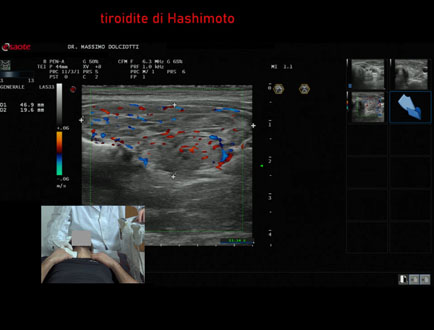

Data inserimento: 03/03/2025

Ecografia del: 02/12/2024

Strumento: Esaote MyLab Eight

Sonda: Lineare Multifrequenza 3-13 MHz

Età Paziente: M 32 anni

Motivazione dell'esame: follow up di tiroidite

Commento all'esame: le immagini ed il video documentano la ghiandola tiroidea a morfovolumetria nei limiti di norma ed ecostruttura diffusamente disomogenea, per patologia diffusa del tipo tiroidite di Hashimoto.

Conclusioni: tiroidite di Hashimoto (Hashimoto's Thyroiditis).

Presentazione: Dr. Massimo Dolciotti - Ancona